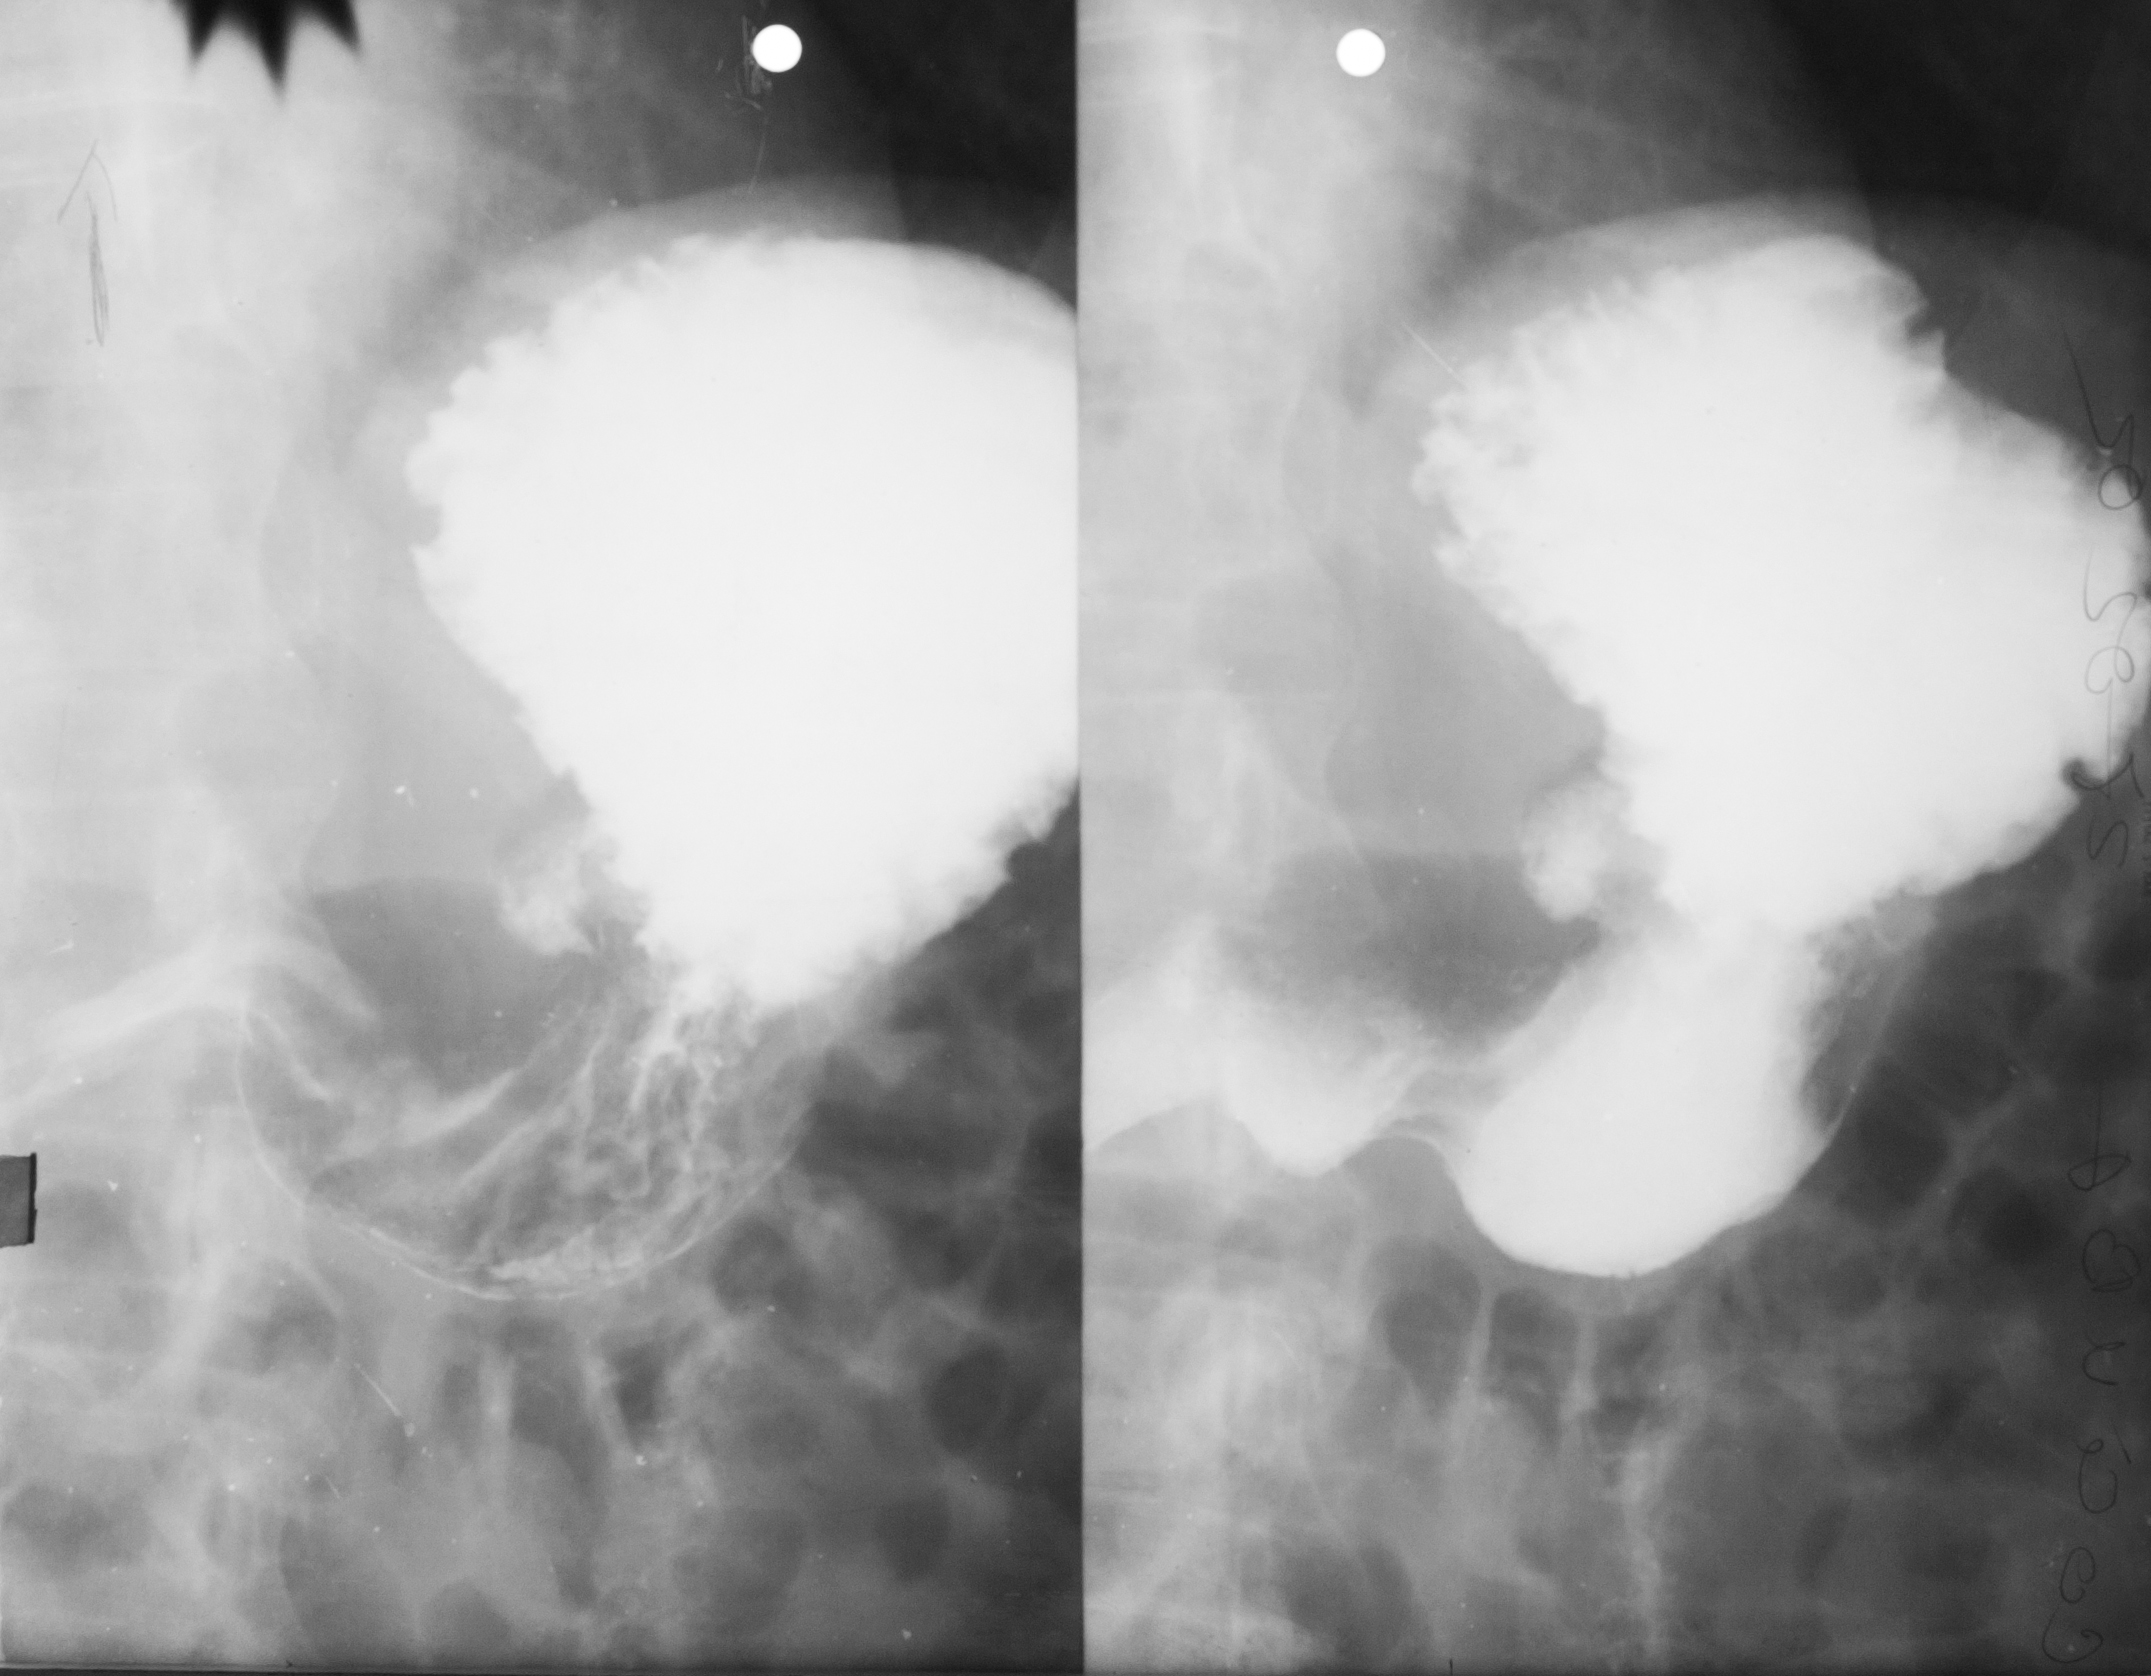

: IRIGOGRAFIE

Aspect radiologic al irigoscopiei unde recunoastem cec ascendent, flexura hepatica , transvers care este ptozat si e singura modificare care nu este neaparat patologica, flexura splenica, colon desccendent, sigmoid si rect. Absolut normal pentru persoana relativ in varsta

DEFECT DE UMPLERE (IRIGOSCOPIE/IRIGOGRAFIE)

Este rotund, bine net liniar delimitat, probabil ceva polip

DIVERTICULI (IRIGOGRAFIE)

Multiple imagini de aditie la nivelul cadrului colic

STENOZA MALIGNA = ADENOCARCINOM DE COLON

Tot irigografie cu zona de stenoza la nivelul colonului transvers, vedem coloana vertebrala si colon descendent, cu contur neregulat la extremitati, cu aspect de cotor de mar

Tot irigografie.

Zona de stenoza la nivelul colonului descendent si retrodilatatie cu aspect de pantalon de golf, proces infiltrativ la nivelul colonului. Mai putin frecvent decat adenocarcinomul

PROCES NEOPLAZIC CU STENOZĂ

Colon descendent, sigma, zona de stenoza fara mucoasa la nivelul acestei zone, proces neoplazic.

NEOPLASM

Aspect de cotor de mar cu stenoza, contur neregulat, retrodilatatii,lipsa lizereului de siguranță,deci lipsa mucoasei la acest nivel. Neoplasm